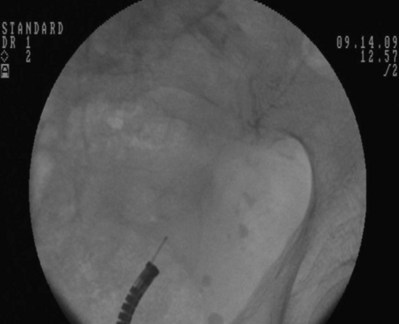

Figure 7–9 The 8 portion has been removed. Asterisk shows the faint outline of the 10 portion along the guidewire.

After obtaining bladder access with either a flexible or rigid cystoscope, a floppy-tip guidewire is advanced into the ureteral meatus and coiled in the renal pelvis using fluoroscopy, the cystoscope is then removed and an 8- to 10-Fr coaxial dilator is advanced under fluoroscopy until the 10-Fr sheath is at the urethral meatus. The 8-Fr internal dilator is removed, leaving a conduit (10-Fr outer sheath) through which to advance the stent.

The ureteral stent is then advanced over the guidewire through the 10-Fr sheath by using a pusher with a small fluoroscopically visible metal band at its tip. The metal tip pusher is advanced under fluoroscopic control to the upper border of the pubic symphysis in male patients and lower border in female patients, while stabilizing the position of the lower end of the stent. The 10-Fr sheath and subsequently the guidewire are removed, allowing the stent to curl in the bladder.